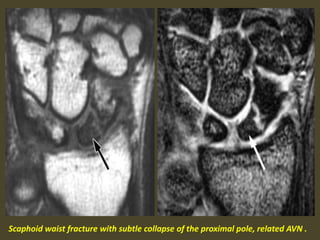

Scaphoid waist fracture with subtle collapse of the proximal pole, related AVN .

Diffuse enhancement of scaphoid proximal pole has good correlation

with stage group I, patchy enhancement have correlation with

grade II and III and enhancement with complete necrosis.

Preiser's disease. Coronal inversion recovery (A) and fast spin echo (B) images:

1. a bone marrow edema pattern in the scaphoid (black arrow) and 2.

avascular necrosis of the proximal pole (white arrow). No fracture is visible.

Idiopathic avascular necrosis of the scaphoid (Preiser’s disease)